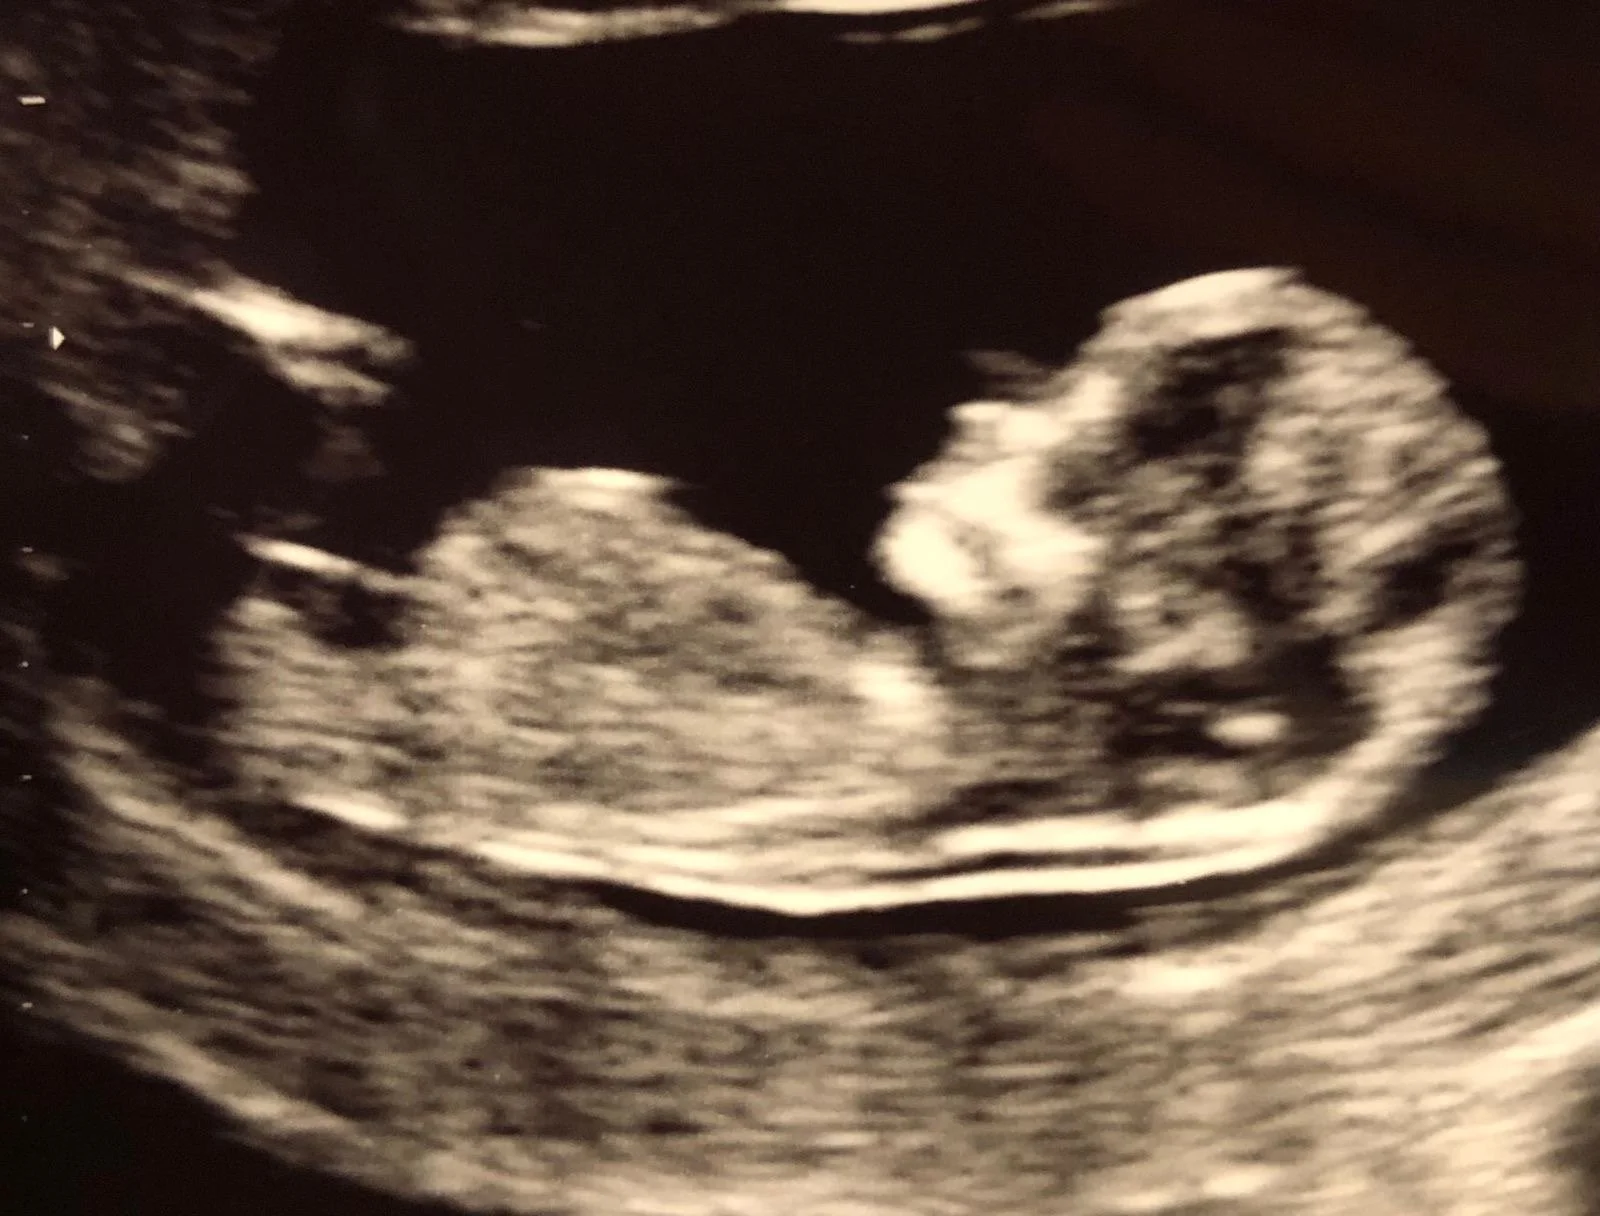

ScanSanctuary Client Scan Examples